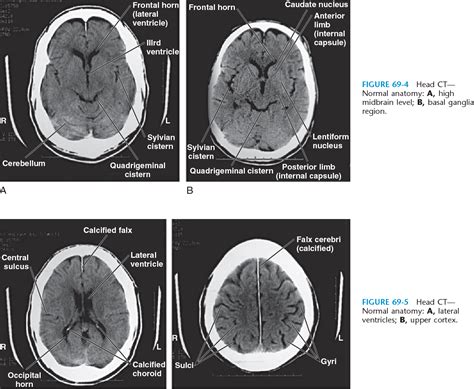

A Normal Ct Head Png serves as a benchmark for comparing abnormal scans. It helps radiologists and neurologists identify deviations from the standard anatomy, which can indicate various medical conditions. The normal scan provides a clear picture of the brain’s structure, including the ventricles, cerebral cortex, and other critical areas.

Interpreting a Normal Ct Head Png involves a thorough understanding of brain anatomy. Radiologists look for several key features:

• Ventricles: The ventricles are fluid-filled spaces in the brain. In a normal scan, they should be symmetrical and of normal size.

• Cerebral Cortex: The cerebral cortex should appear smooth and uniform, without any signs of atrophy or lesions.

• White Matter: The white matter should be intact, without any signs of demyelination or other abnormalities.

• Blood Vessels: The major blood vessels should be clearly visible and free of any blockages or aneurysms.